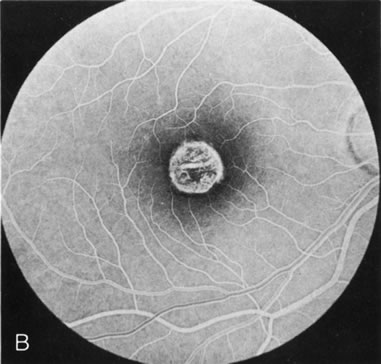

In CACD the bilateral macular lesions are solitary, circumscribed, and circular or ovoid in shape. They are unassociated with other findings such as drusen or flecks. FA will confirm the well-circumscribed area of choriocapillaris atrophy and further document that there are no associated findings that would lead to secondary choroidal atrophy in disorders such as age-related macular degeneration, Stargardt's fundus flavimaculatus, or dominant drusen of Bruch's membrane11 (Fig. 7 A and B).

Fig. 7. Central areolar choroidal dystrophy. The presence of choroidal atrophy in this well-circumscribed macular lesion (A) is confirmed by persistent visualization of the larger choroidal vessels as seen on angiography (B). Peripapillary (pericentral) choroidal dystrophy. The areas of choroidal atrophy are well-demarcated and contrast with the areas of normal choroid (C, D). Crystalline retinopathy (of Bietti). The areas of choroidal atrophy correspond to areas of the retina where crystals are not present (E, F).

Peripapillary (Pericentral) Choroidal Dystrophy

Peripapillary choroidal atrophy radiates from the optic nerve along the temporal vascular arcades. The macula is affected later in the course, and this is usually responsible for the onset of visual symptoms. FA shows the choroidal atrophy and the early macular changes (Fig. 7C and D).